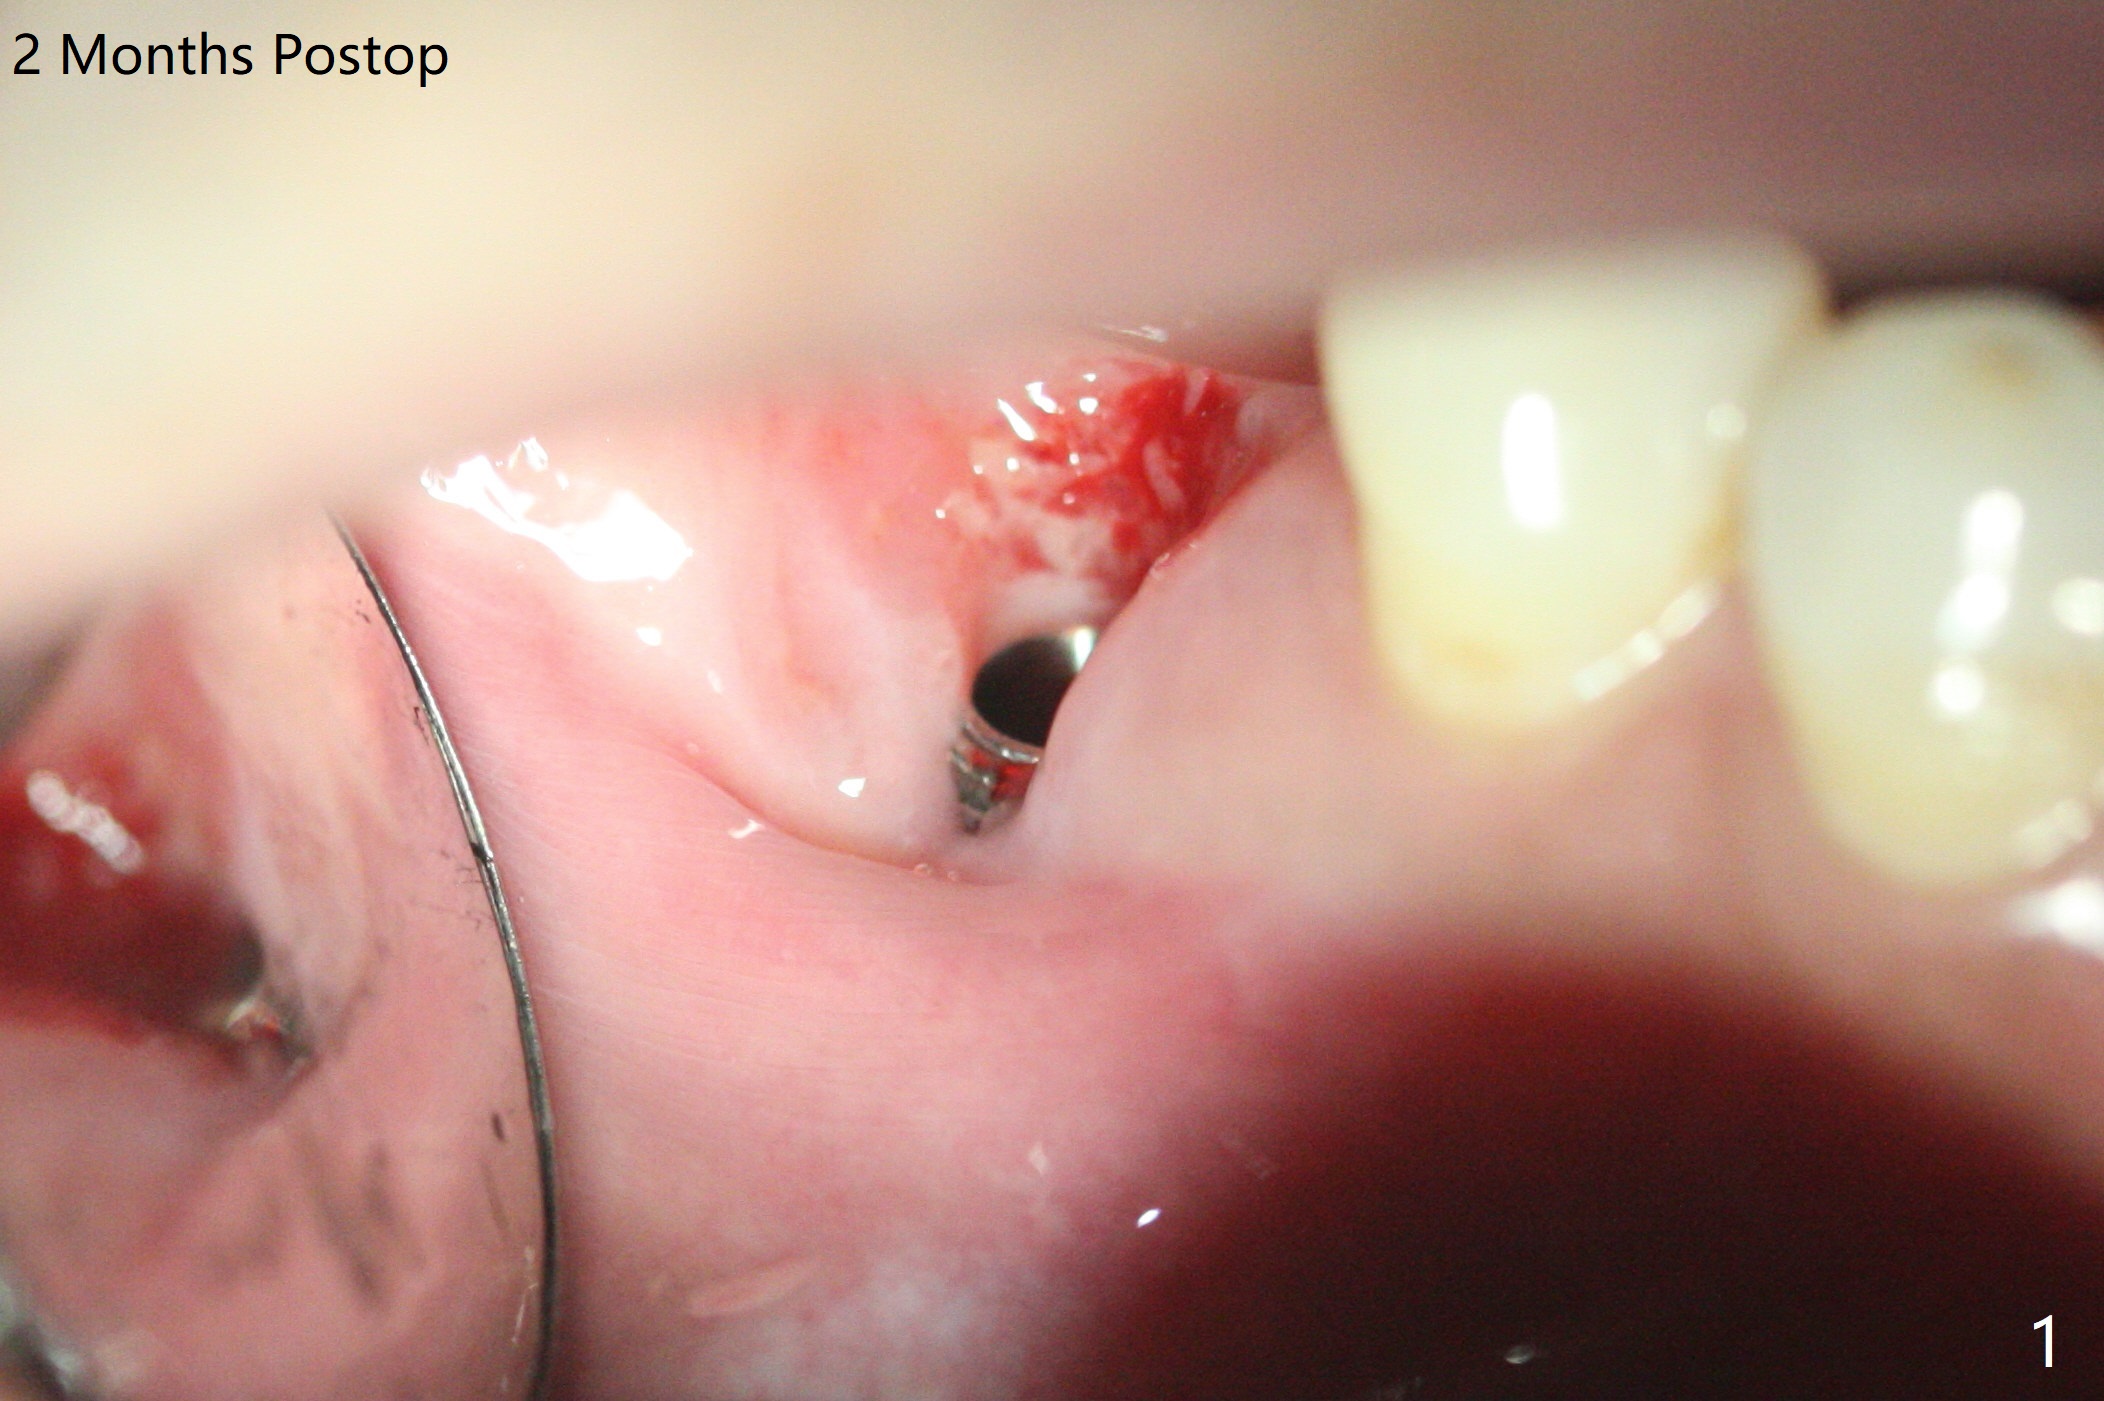

In spite of use of water pik, the coronal threads of the implant at #30 remain exposed 2 months postop (Fig.1). Envelop incision with mesial and distal accessory release ones reveals buccal bony defect (Fig.2). After 2nd spin (1500 RPM for 10 minutes), PRF forms in the red tube (Fig.3 yellow gel-like). Following use of Titanium brush, sticky bone is place (not so bone block-like, Fig.4), followed by a large piece of PRF membrane (from the red tube of Fig.3), Cytoplast (Fig.5,6 white porous) and a small piece of PRF membrane (from the white tube, next to the thin gingiva). The distal (Fig.6 D) and mesial (Fig.7 M) flaps are approximated (arrows without suture) as much as possible as well as lingual. 4-0 Polyglycolic Acid suture is used. Periodontal dressing dislodges 5 days postop. When the patient returns 1 week postop, he is pain free. Although Cytoplast is exposed, the surrounding gingiva seems to be healthy (Fig.8). Later the permanent crown of #31 is temporarily cemented with OHI. It appears that Cytoplast could be used to cover PRF membranes for soft tissue defect, followed by immediate provisional at the stage of immediate implant. The discolored (apparently contaminated) Cytoplast seems to be expelled 6 weeks postop (Fig.9). When the latter is removed, the soft tissue looks normal (Fig.10). Two weeks later, the apparently normal, but thin gingiva forms over the former granulation tissue (Fig.11 *, as compared to Fig.10). There is not enough bone coronal to the implant plateau 2 months post graft (Fig.12). Three months later, bone graft will be re-placed possibly with uncover.